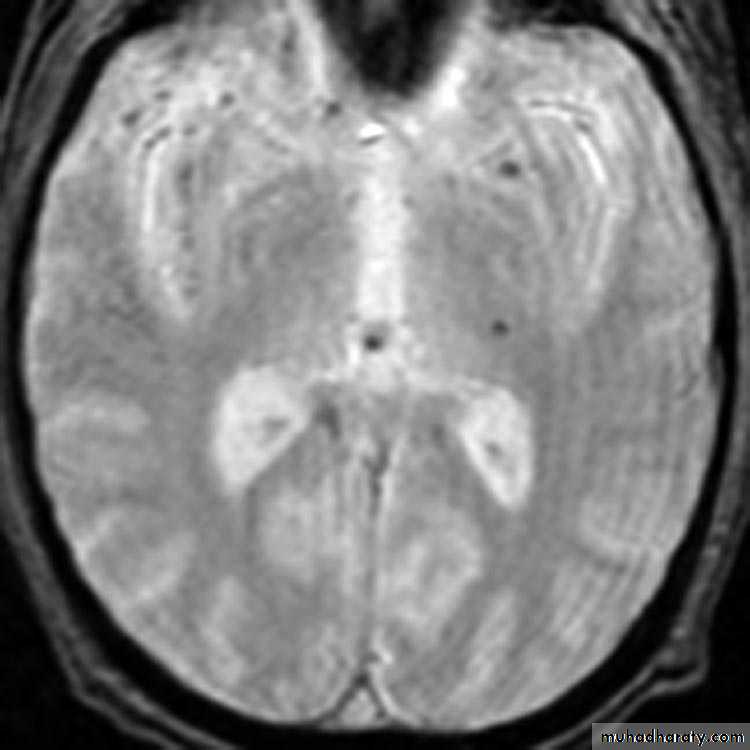

1. Diffuse Axonal Injury

Prolonged post-traumatic state in which there is loss of consciousness from the time of injury that continues beyond 6 hours.Occurs as a result of mechanical shearing at the grey-white matter interface.

This causes disruption and tearing of axons, myelin sheaths and blood capillaries.

Severity can range from mild damage with confusion to coma and even death.